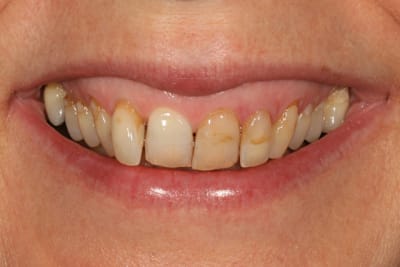

Si on regarde la photo 3, sourire de face, tu doit faire 10 céram en haut, de

5 à 5 (et là, je ne retiens pour pas dire 12...)

Ensuite, tu fais rien pour la couleur en bas ? OK

pour l'attrition ? OK, au pire une goutière nocturne.

Si tu touches 6 dents (3 à 3), ben le sourire ne sera tjs pas trop beau...juste mon pt de vue.

merci à ceux qui ont participé, vous m'avez fait penser à des choses que je n'avais pas imaginé pour le traitement de ma patiente

et effectivement, si on avait voulu faire un sourire parfait, on aurait pu faire ortho, alignement des collets, facettes, voire une chirurgie de la lèvre pour le sourire gingival

la patiente n'est pas du tout venue pour ça, et je ne me vois pas lancer tout ça pour une patiente qui ne se plaint que de ses composites et un peu de sa 12

je lui ai proposé un éclaircissement, de refaire les compos, et de voir après si on pouvait rentrer la 12 avec un moyen ortho amovible (invisalign, inman aligner ou autre)

puisqu'elle a refusé tout net les bagues

je n'avais pas pensé à corriger sa classe II, ni a tout couronner ou facetter pour "ressortir" les dents très rentrées ; ni même a aligner ses collets en fait.

pour cette patiente qui n'avait pas de grandes exigences, je me suis auto limité en voulant être le moins iatrogène possible.

comme quoi poster m'aura été utile, j'avais pas tout vu ni tout envisagé.

je reste content de mon traitement, tout simplement parce que la patiente est très contente.

elle n'a même pas eu envie d'essayer de bouger la 12 après (et tant mieux parce que maintenant qu'on en a discuté, ça aurait surement été galère de ne toucher que ça)